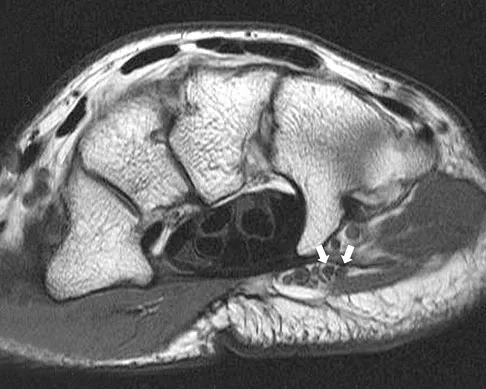

A patient notes pain under the first metatarsophalangeal joint following a soccer injury. The MRI scans shown in Figures 27a and 27b reveal what pathologic finding?

Explanation